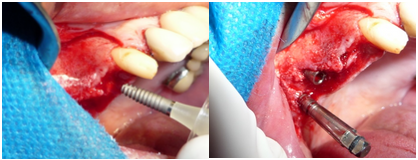

Em seguida é realizada a instalação dos implantes nos nichos pré–confeccionados. Devido à boa disponibilidade óssea obtida pela técnica de elevação de soalho de seio maxilar foi possível a instalação de três implantes de 13mm de comprimento. Os implantes utilizados foram da marca Implacil de hexágono interno com ø de 3,5mm na região do 14, e de ø 4,0mm na região de 15 e 16. Todos com boa estabilidade primária (figura 8).